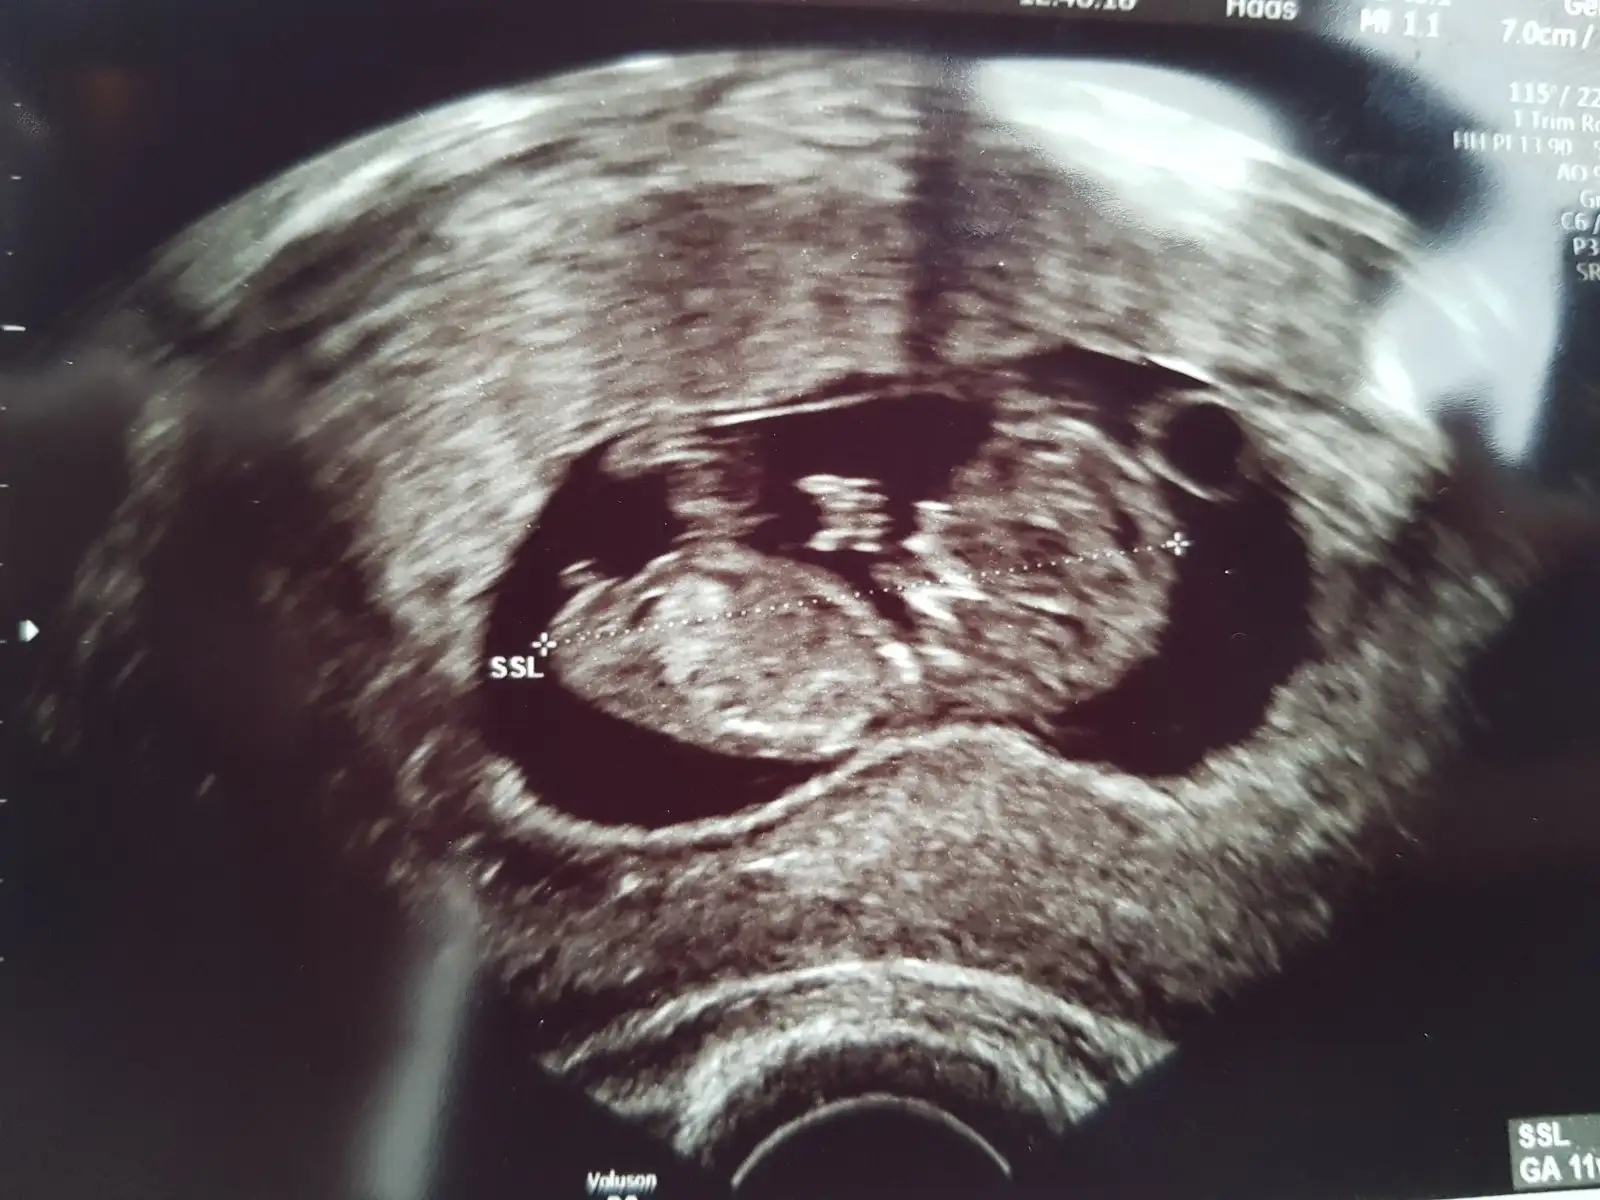

Yaa şimdiden belli olma anlaşılma ihtimali var mı? Yarın hemen giderim valla doktoraKızlar bugün kontrolüm vardı. Bebişim maşallah baya büyümüş. 4,31 cm..haftasindan 1 hafta önde gidiyormuş.kizlar birde ultrason resmine gore pipi ye benzeyen birşey var.doktora sordum .olabilir benziyor ama ben bunu henüz size söyleyemem çünkü çok erken göbek kordonu da olabilir dedi..ay çok merak ediyorum..anlayaniniz var mi ultrason resimlerinden.

Masallah. Genital nub teorisi diye bir forum var orada yardımcı olurlarKızlar bugün kontrolüm vardı. Bebişim maşallah baya büyümüş. 4,31 cm..haftasindan 1 hafta önde gidiyormuş.kizlar birde ultrason resmine gore pipi ye benzeyen birşey var.doktora sordum .olabilir benziyor ama ben bunu henüz size söyleyemem çünkü çok erken göbek kordonu da olabilir dedi..ay çok merak ediyorum..anlayaniniz var mi ultrason resimlerinden.

Vajinal usg ile bakılmış maşallah büyümüş meleğin ,ne sık aralıklarla doktor kontrolüne gidiyorsun

Benımde erkekmiş diye geçtiEvet canim vaginal usg.4 hafta da bir kontrole